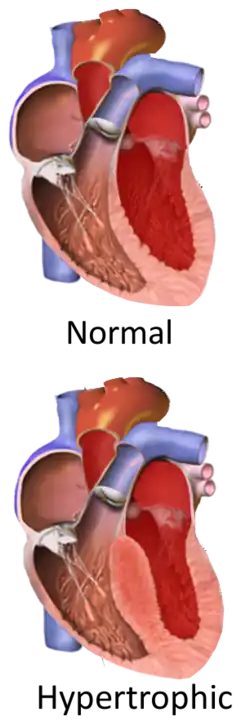

Hypertrophic cardiomyopathy (HCM, or HOCM when obstructive) is a condition in which muscle tissues of the heart become thickened without an obvious cause.[8] The parts of the heart most commonly affected are the interventricular septum and the ventricles.[10] This results in the heart being less able to pump blood effectively and also may cause electrical conduction problems.[3] Specifically, within the bundle branches that conduct impulses through the interventricular septum and into the Purkinje fibers, as these are responsible for the depolarization of contractile cells of both ventricles.[11]

Ventricular hypertrophy causes a dynamic pressure gradient across the left ventricular outflow tract (LVOT), which is associated with further narrowing of the outflow during systole. Pulling of the mitral valve leaflets towards the septum contributes to the outflow obstruction. This pulling is thought to occur by several proposed mechanisms, including that the flow of blood through the narrowed outflow tract results in it having a higher velocity, and less pressure through the Venturi effect.[17] This low pressure then causes the anterior leaflet of the mitral valve to be pulled into the outflow tract, resulting in further obstruction.[32]